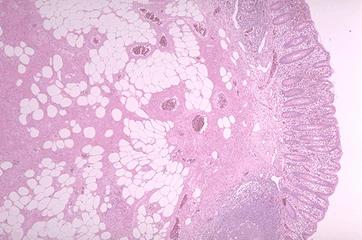

Lipoangioma in the ascending colon removed by an endoscopical polypectomy.

Non-epithelial tumors/Angiolipoma

Large intestine(Colon)/Ascending colon

Histology

10 - 14